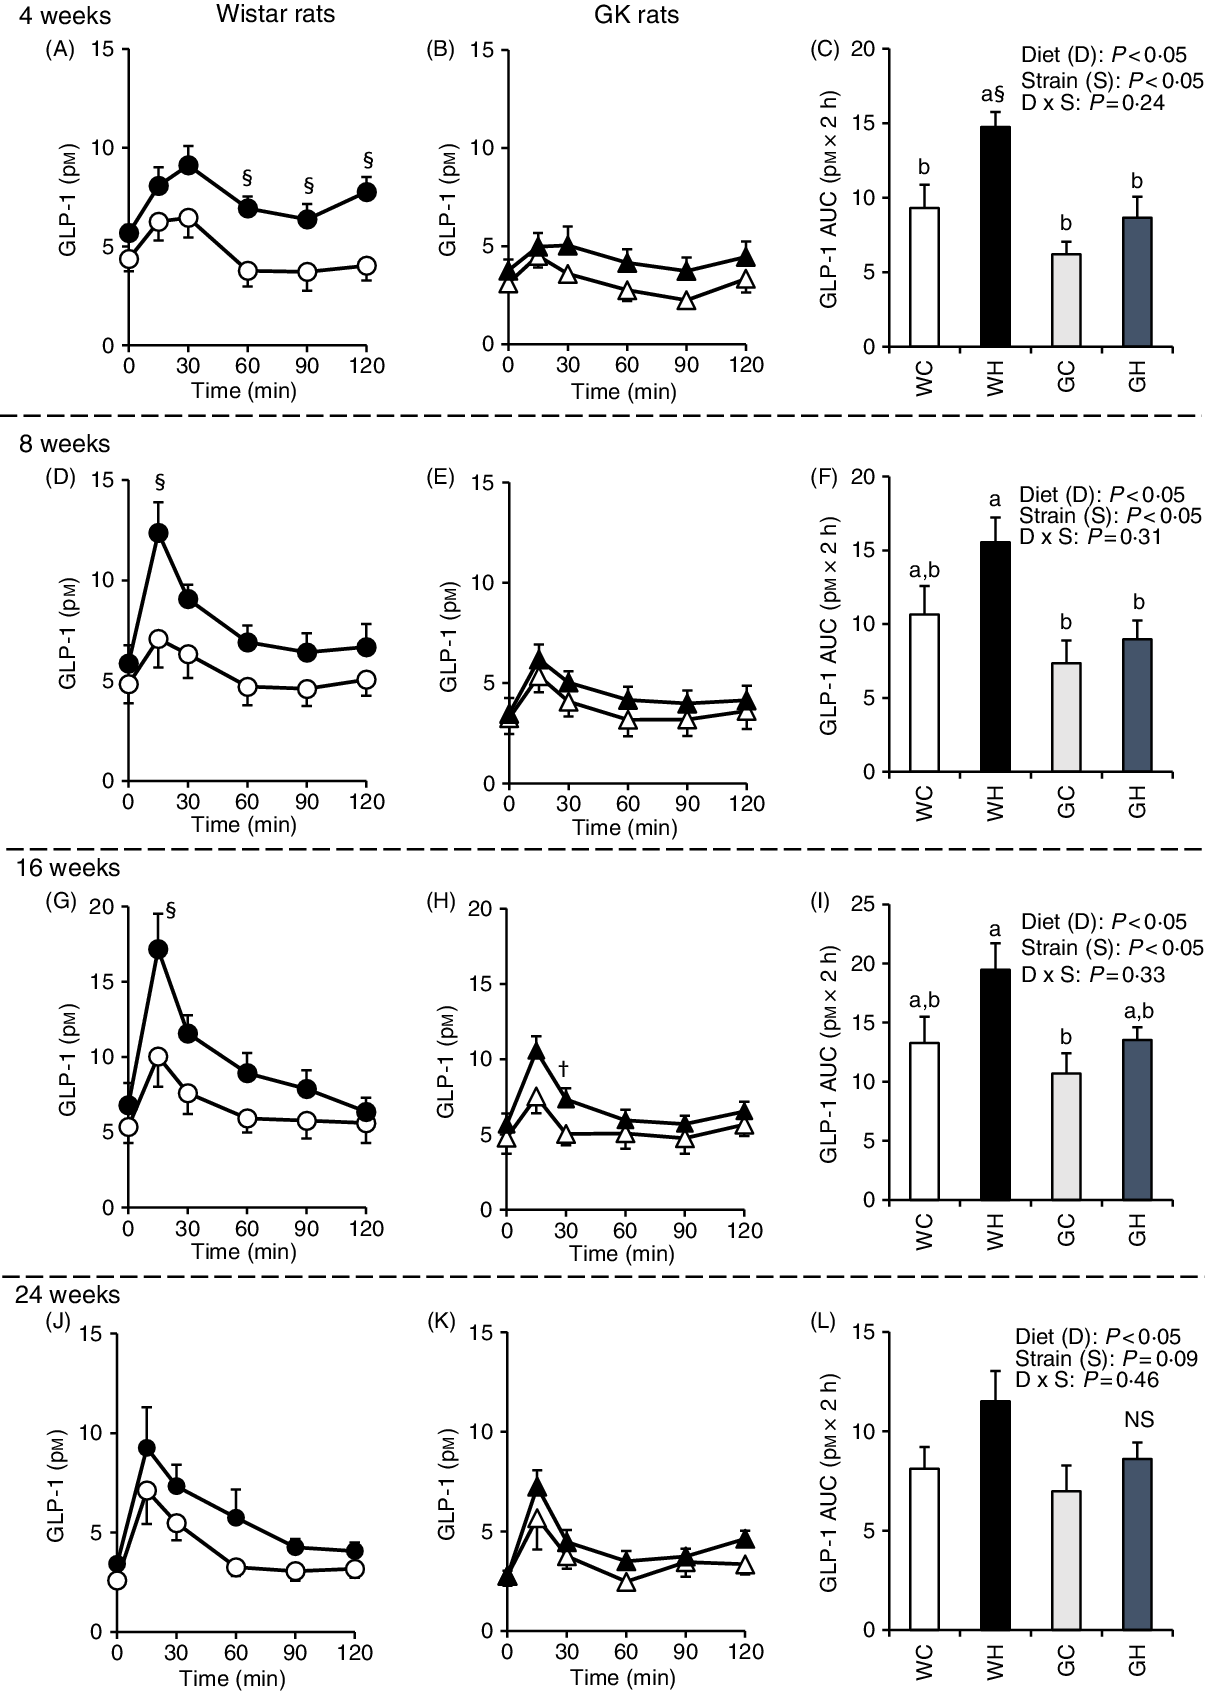

Postprandial glucagon-like peptide-1 response

GLP-1 responses were higher in the WH group compared with those of the WC group (at 60–120 min and the AUC after 4 weeks, as well as at 15 min after 8 and 16 weeks) as shown in Fig. 3(A), (D) and (G), whereas GLP-1 responses and the AUC were observed to be similar in the GH and GC groups throughout the experimental period (Fig. 3(C), (F), (I) and (L)). Likewise, two-way ANOVA showed significant effects of diet and/or of strain on postprandial GLP-1 AUC in all MTT.

Fig. 3. Postprandial glucagon-like peptide-1 (GLP-1) responses under meal tolerance test (MTT) after 4-, 8-, 16- and 24-week feeding period. Wistar rats and diabetic Goto-Kakizaki (GK) rats were fed either a control diet or high-fat/high-sucrose (HFS) diet for 4, 8, 16 and 24 weeks before conducting MTT. After an overnight fasting, blood samples were collected from the tail vein before (0 min) and after oral administration of a liquid diet (Ensure H, 10 ml/kg body weight). ![]() , Wistar rats fed the control diet (WC);

, Wistar rats fed the control diet (WC); ![]() , Wistar rats fed the HFS diet (WH);

, Wistar rats fed the HFS diet (WH); ![]() , GK rats fed the control diet (GC);

, GK rats fed the control diet (GC); ![]() , GK rats fed the HFS diet (GH). Data are mean values with their standard errors (n 6–9 rats in each group). a,b Mean values with unlike letters are significantly different (P < 0·05, Tukey–Kramer’s test). § Significant differences between mean values of the WC and WH groups; † significant difference between mean values of the GC and GH groups (P < 0·05, Student’s t test). P values of two-way ANOVA for diet, strain and strain-by-diet interactions are shown in the panels. NS indicates that there was no significant difference between the treatments.

, GK rats fed the HFS diet (GH). Data are mean values with their standard errors (n 6–9 rats in each group). a,b Mean values with unlike letters are significantly different (P < 0·05, Tukey–Kramer’s test). § Significant differences between mean values of the WC and WH groups; † significant difference between mean values of the GC and GH groups (P < 0·05, Student’s t test). P values of two-way ANOVA for diet, strain and strain-by-diet interactions are shown in the panels. NS indicates that there was no significant difference between the treatments.